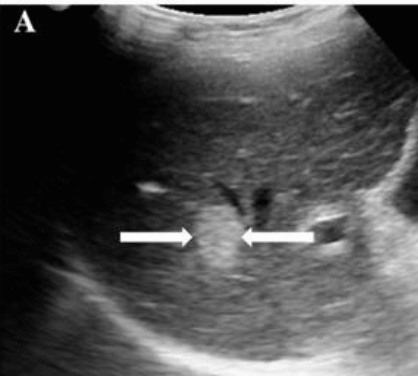

암부위와 정상조직의 경계가 뚜렷한 것을 말한다. 종양 내에 섬유성의 격벽이 존재하며 이것에 의해 소결절로 다시 구분된다. 간세포암의 초음파상은 직경 3cm 이상의 결절형이 특징적이며 저에코의 격벽과 경계가 되는 에코레벨이 다른 소결절이 모자이크 패턴(mosaic pattern)으로 관찰되며 피막에는 달무리(halo)가 존재한다.

① <2cm small hcc sono finding

- well define

- round shape

- hypoechoic / hyperechoic, bright loop sing pattern (지방화, 탈분화 동반 경우 드물게 보임)

- irregular / indistinct margin

- halo (-)

<2cm small hcc sono features ② 2~3cm hcc sono finding

- hypo-hyperechoic

- ireegular margin

- halo(+) 종양이 2cm 이상 커지면 주위조직을 밀게 되면서 피막이 형성되면서 저에코 테두리가 나타남. (간세포암의 40~50%)